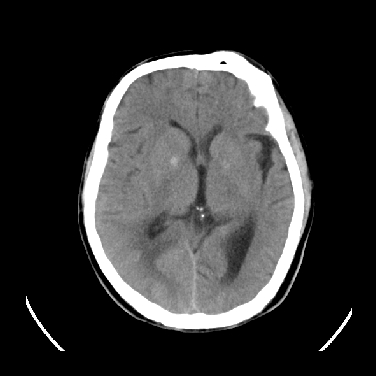

男,45岁,左侧肢体乏力1周。ex:胸片示:两肺团块状、斑片状密度增高影,其内可见小空洞。支纤镜、经皮肺穿示:干酪样物。

结合病史考虑结核性脑炎脑膜炎,伴脑脓肿形成

考虑右侧顶叶脑脓肿形成。

同意“考虑结核性脑炎脑膜炎,伴脑脓肿形成”的意见,不轻易怀疑肿瘤。

考虑结核性脑炎脑膜炎,伴脑脓肿形成。

考虑右侧顶叶脑脓肿(结核性?)。

结核性脑脓肿可能大

结合病史考虑结核性脑炎脑膜炎,伴脑脓肿形成,囊变转移瘤不除外